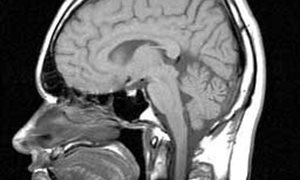

Voor 41 patiënten gaven de behandeld artsen aan dat die zonder twijfel in een vegetatieve toestand verkeerden. Na een nieuwe, nauwkeurige diagnose waren dat er nog 24. Er zijn dus weinig vegetatieve patiënten in Nederland, ongeveer 3 patiënten per twee miljoen inwoners. Uit eerder onderzoek blijkt dat dit het laagste aantal ter wereld is. Verder blijkt dat bij de helft van de patiënten de hersenschade is ontstaan door zuurstoftekort tijdens hartstilstand en reanimatie.